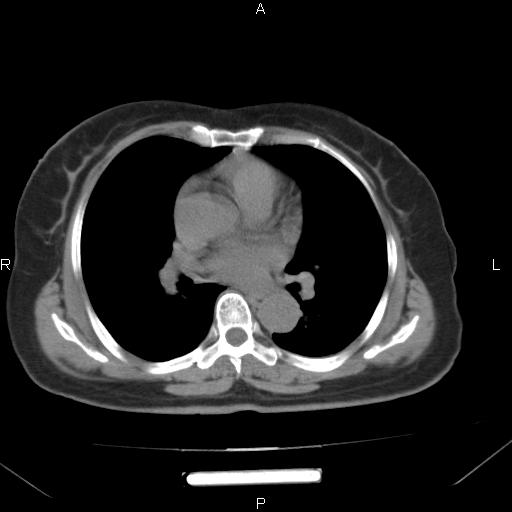

胸腺瘤

女、63Y 双眼睑下垂,早轻晚重。 胸腺瘤???

结果胸腺瘤